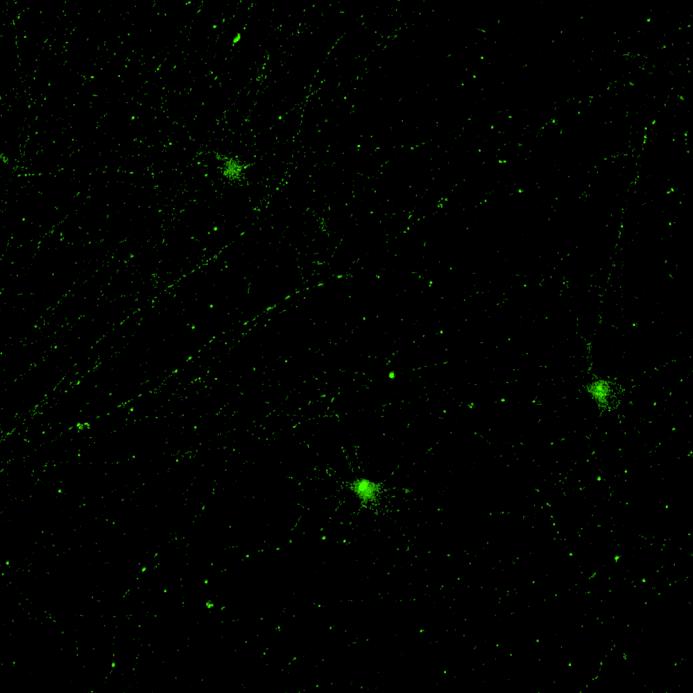

Live imaging of tau aggregation using lentiviral systems

Overexpressed full-length 0N4R-EGFP tau

• Wildtype neurons were transduced with a lentivirus to express a full-length 4R tau isoform with a familial frontotemporal dementia P301L mutation labelled with EGFP

• Neurons were then exposed to recombinant tau preformed fibrils (PFFs) and imaged

• Increasing over time, PFF exposure induced areas of bright EGFP-positive aggregates of full-length tau, and aggregation of the K18 fragment FRET pair as seen by positive normalised FRET (NFRET) signal

• K18 PFFs with P301L mutation induced aggregation more readily than full length 2N4R PFFs in both systems